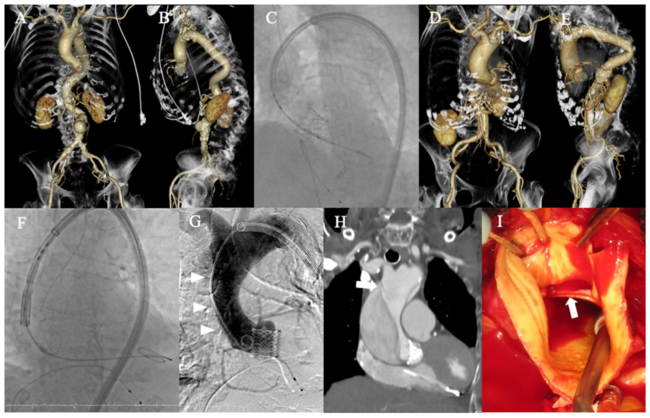

Case 1. An 88-year-old woman with saccular abdominal aortic aneurysm and tortuous aorta underwent transfemoral TAVR using a 65-cm 18-Fr DrySeal sheath (W.L. Gore) (Figures 1A-1C). A 23-mm Sapien 3 valve (Edwards Lifesciences) was uneventfully deployed and demonstrated excellent valve function.

Case 2. An 84-year-old woman with tortuous aorta and horizontal aortic root underwent transfemoral TAVR (Figures 1D, 1E). A 65-cm 18-Fr DrySeal sheath was inserted using a stiff guidewire and a 23-mm Sapien valve was deployed (Figure 1F). Postprocedure aortography showed an ascending aortic dissection (Figure 1G) and computed tomography and surgical inspection determined the dissection entry at the distal ascending aorta, which was corresponding to the tip of the long sheath (Figures 1H, 1I).